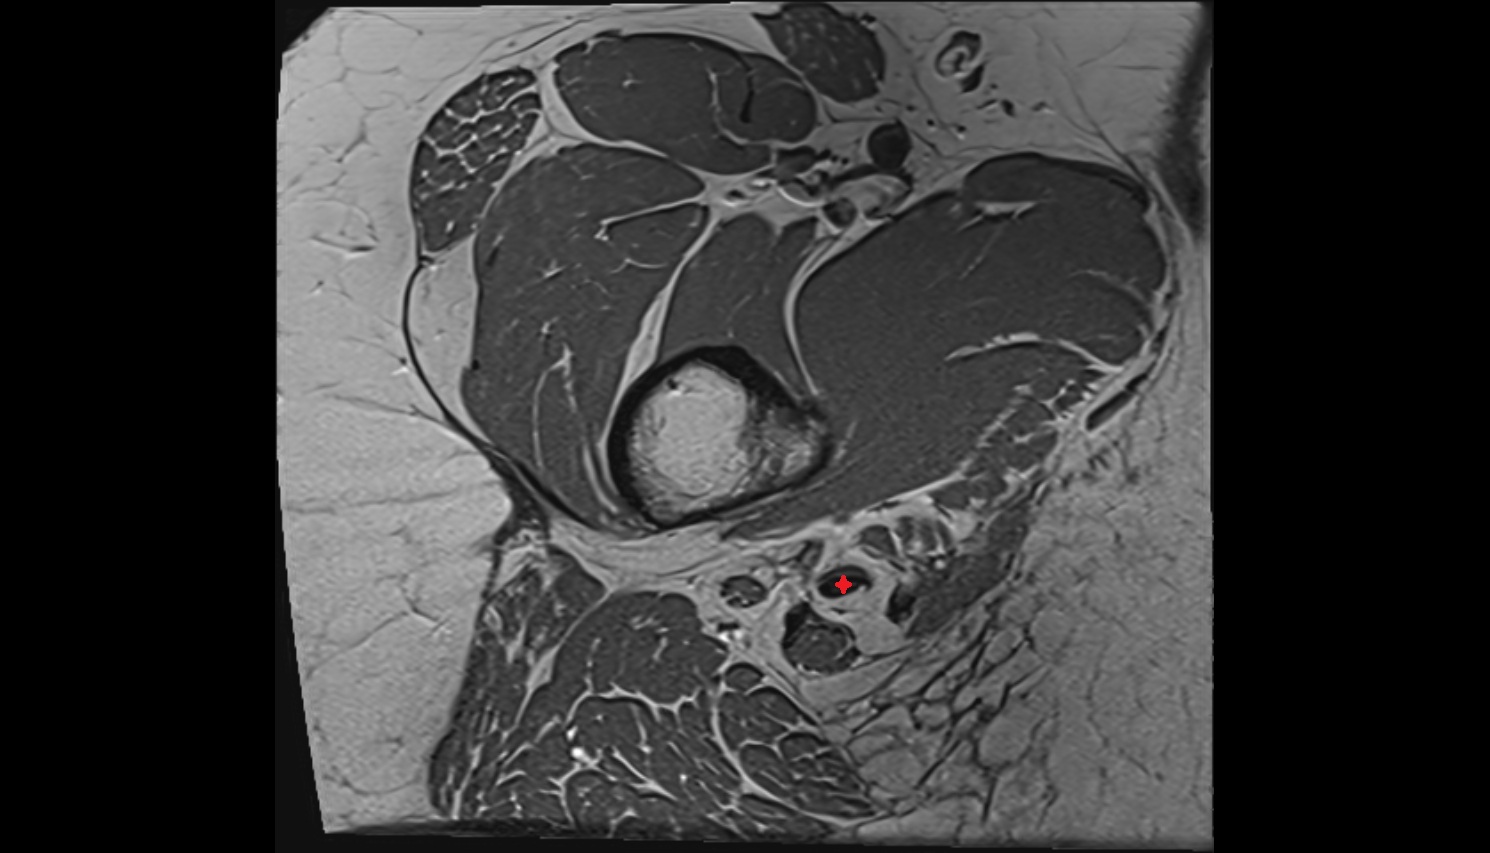

- Hip joint